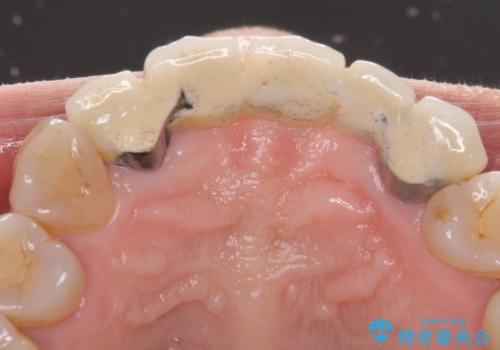

- アンバランスな色や形、歯肉ラインの黒い縁が目立ってしまったブリッジの作り直しを希望して来院された患者様です。

装着されていたブリッジは、支台となっている歯と欠損している歯で色が大きく異なっていましたが、オールセラミックとしたことで、全体的に色調の整った仕上がりとなりました。